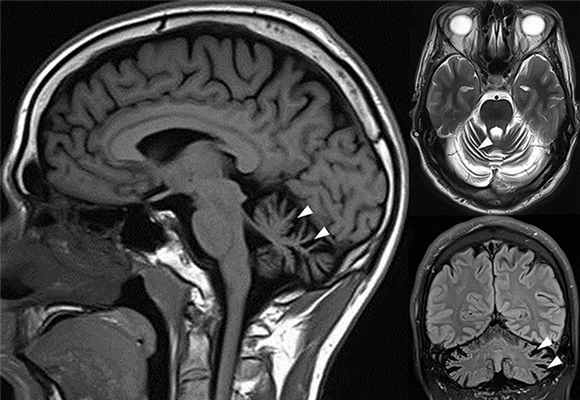

Смерть наступает в первые месяцы жизни. Макроскопически: атрофия больших полушарий и мозжечка, гидроцефалия с образованием в области истонченной коры кистозных полостей. Гистологически мозг незрелый (фетопатия), клетки коры разбухшие, содержат продукты накопления. Имеются указания па наличие судано-фильных «пенистых» клеток в селезенке, печени, легких, тимусе, почках и надпочечниках, что свидетельствует о генерализованном процессе.

Ювенильная форма GM1-ганглиозидоза тип 2. Ферментный дефект имеется со стороны фракции В и С бета-галактозидазы. Болезнь начинается с конца первого года жизни с явлений атаксии, прогрессирует деменция, потеря зрения и потеря моторной деятельности. Смерть наступает в 3—8 лет. Изменения скелета определяются только при рентгенографии («клювы» внизу тел поясничных позвонков). Гепато- и спленомегалии не бывает. Гистологически в отличие от других ганглиозидозов преобладает поражение нейронов мозжечка с последующим глиозом. В мозге содержание ганглиозида GM1 увеличено в 10 раз по сравнению с нормой.

Чаще всего поражается мозжечок, затылочные доли

полушарий мозга с тяжелыми последствиями и

осложнениями для всего организма: атрофия

зрительных нервов, нервные волокна могут утрачивать

свои оболочки, а связи между нервными клетками распадаться.